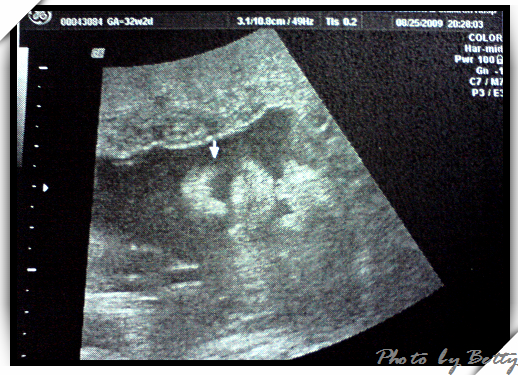

2009年8月25日 32w2d +7.6kg

神奇的是,我們剛好看到小石頭張開嘴巴,伸出舌頭呢

醫生說,他可能正在吃羊水試味道吧..... :P